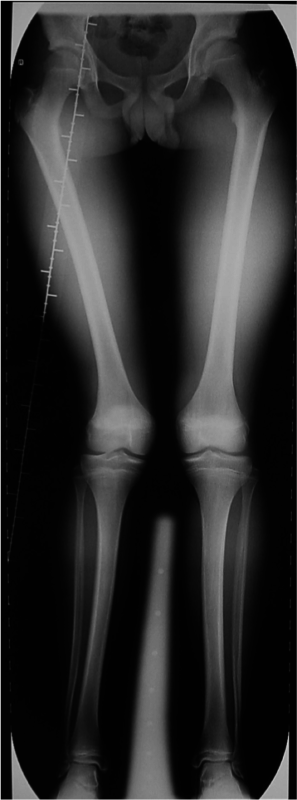

Maschio 13 anni. Esiti di frattura epifiolisi di condilo femorale esterno in eta di 10 anni.

Deformita in valgo del femore e accorciamento di 2,5 cm.

Inizio di correzione delle deformità

Inizio di allungamento